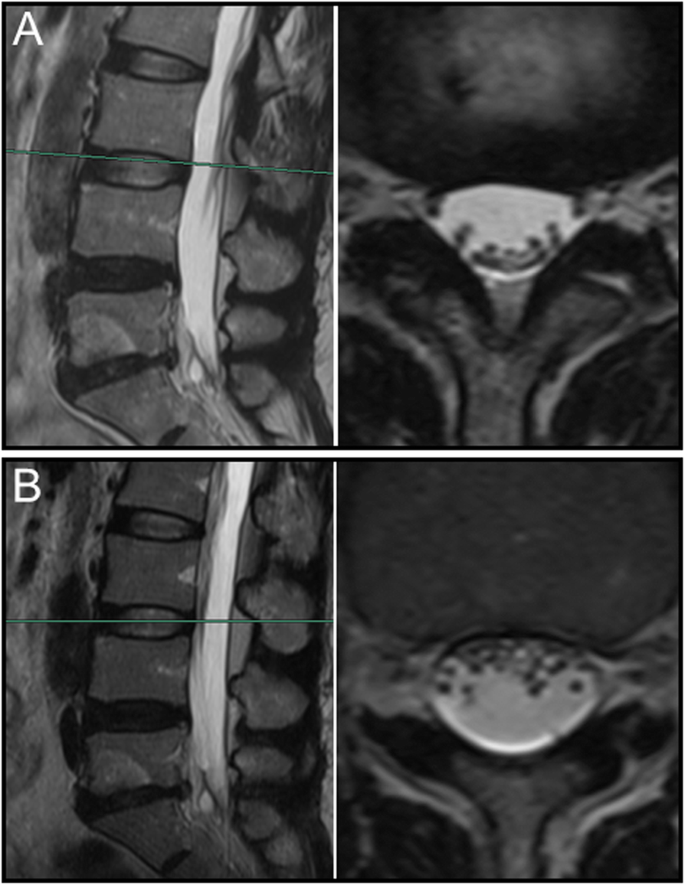

The sedimentation of nerve roots on MR images of various body position

Overall, nerve roots of 48 (85.7%) patients subsided to the ventral side of the dural sac on the prone MR images, although that of 8 (14.3%) patients remain stay in the dorsal side of dural sac. Of the 25 patients with a negative SedSign on supine MR images, the nerve roots settled to the ventral side of the dural sac on prone MR images in 24 patients (Fig. 1). Nerve roots in the remaining 1 patient, who was diagnosed as disc herniation, did not settle to the ventral dural sac (Fig. 2). For all the 31 patients with a positive SedSign, nerve roots subsided to the ventral side of the dural sac on the prone MR images in 24 patients (Table 2, Fig. 3). The nerve roots of the other 7 patients still stay (sequester) in the dorsal dural sac, which were due to single level (Fig. 4) or multiple level stenosis (Fig. 5). The nerve roots in patients with positive SedSign were more likely to stay in the dorsal dural sac on prone position MR images (22.6% vs 4%, P < 0.05, Table 2). In addition, the nerve roots subsided to the left dural sac in all the 5 patients when they were MR imaged on a left lateral position (Fig. 6).